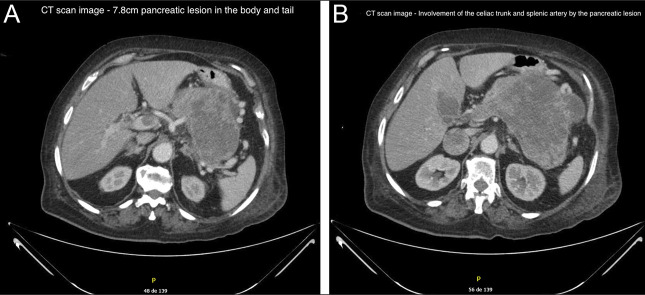

外阴黑色素瘤(VM)是一种罕见的侵袭性恶性肿瘤,具有很高的转移潜力。我们提出一个82岁的妇女谁最初提出阴道出血,并被诊断为VM与淋巴结累及的情况下。尽管进行了手术和姑息治疗,她后来还是出现了脑、淋巴结和胰腺转移。内镜超声引导下细针活检(EUS-FNB)经免疫组化证实胰腺转移。据我们所知,这是第一例用EUS-FNB诊断的VM胰腺转移病例。本病例强调了EUS-FNB在诊断异常部位转移性病变中的重要性。

Vulvar melanoma (VM) is a rare and aggressive malignancy with a high metastatic potential. We present the case of an 82-year-old woman who initially presented with vaginal bleeding and was diagnosed with VM with lymph node involvement. Despite surgical and palliative interventions, she later developed brain, nodal, and pancreatic metastases. Endoscopic ultrasound-guided fine-needle biopsy (EUS-FNB) confirmed pancreatic metastasis through immunohistochemistry. To our knowledge, this is the first reported case of pancreatic metastasis from VM diagnosed by EUS-FNB. This case highlights the importance of EUS-FNB in diagnosing metastatic lesions in unusual locations.